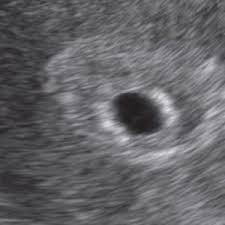

Schmerzen aller 5 min im unterbauch. SSW im Ultraschall noch nicht zu sehen sein. Aber ganz vorne über der Scheide und wenn ich meine hand darauf lege.